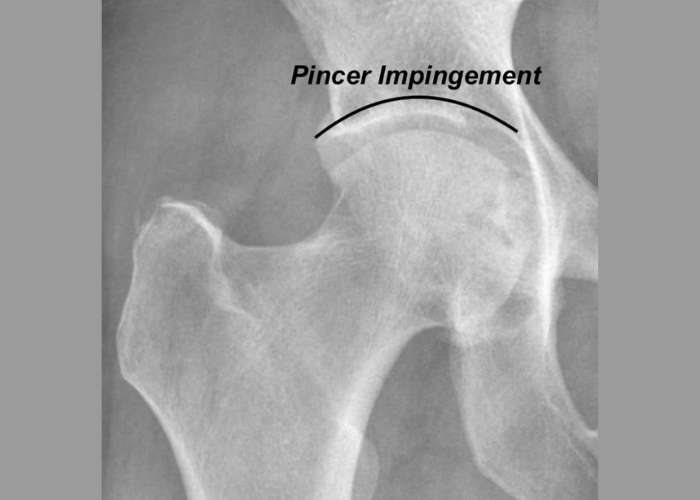

• Pincer Hip Impingement